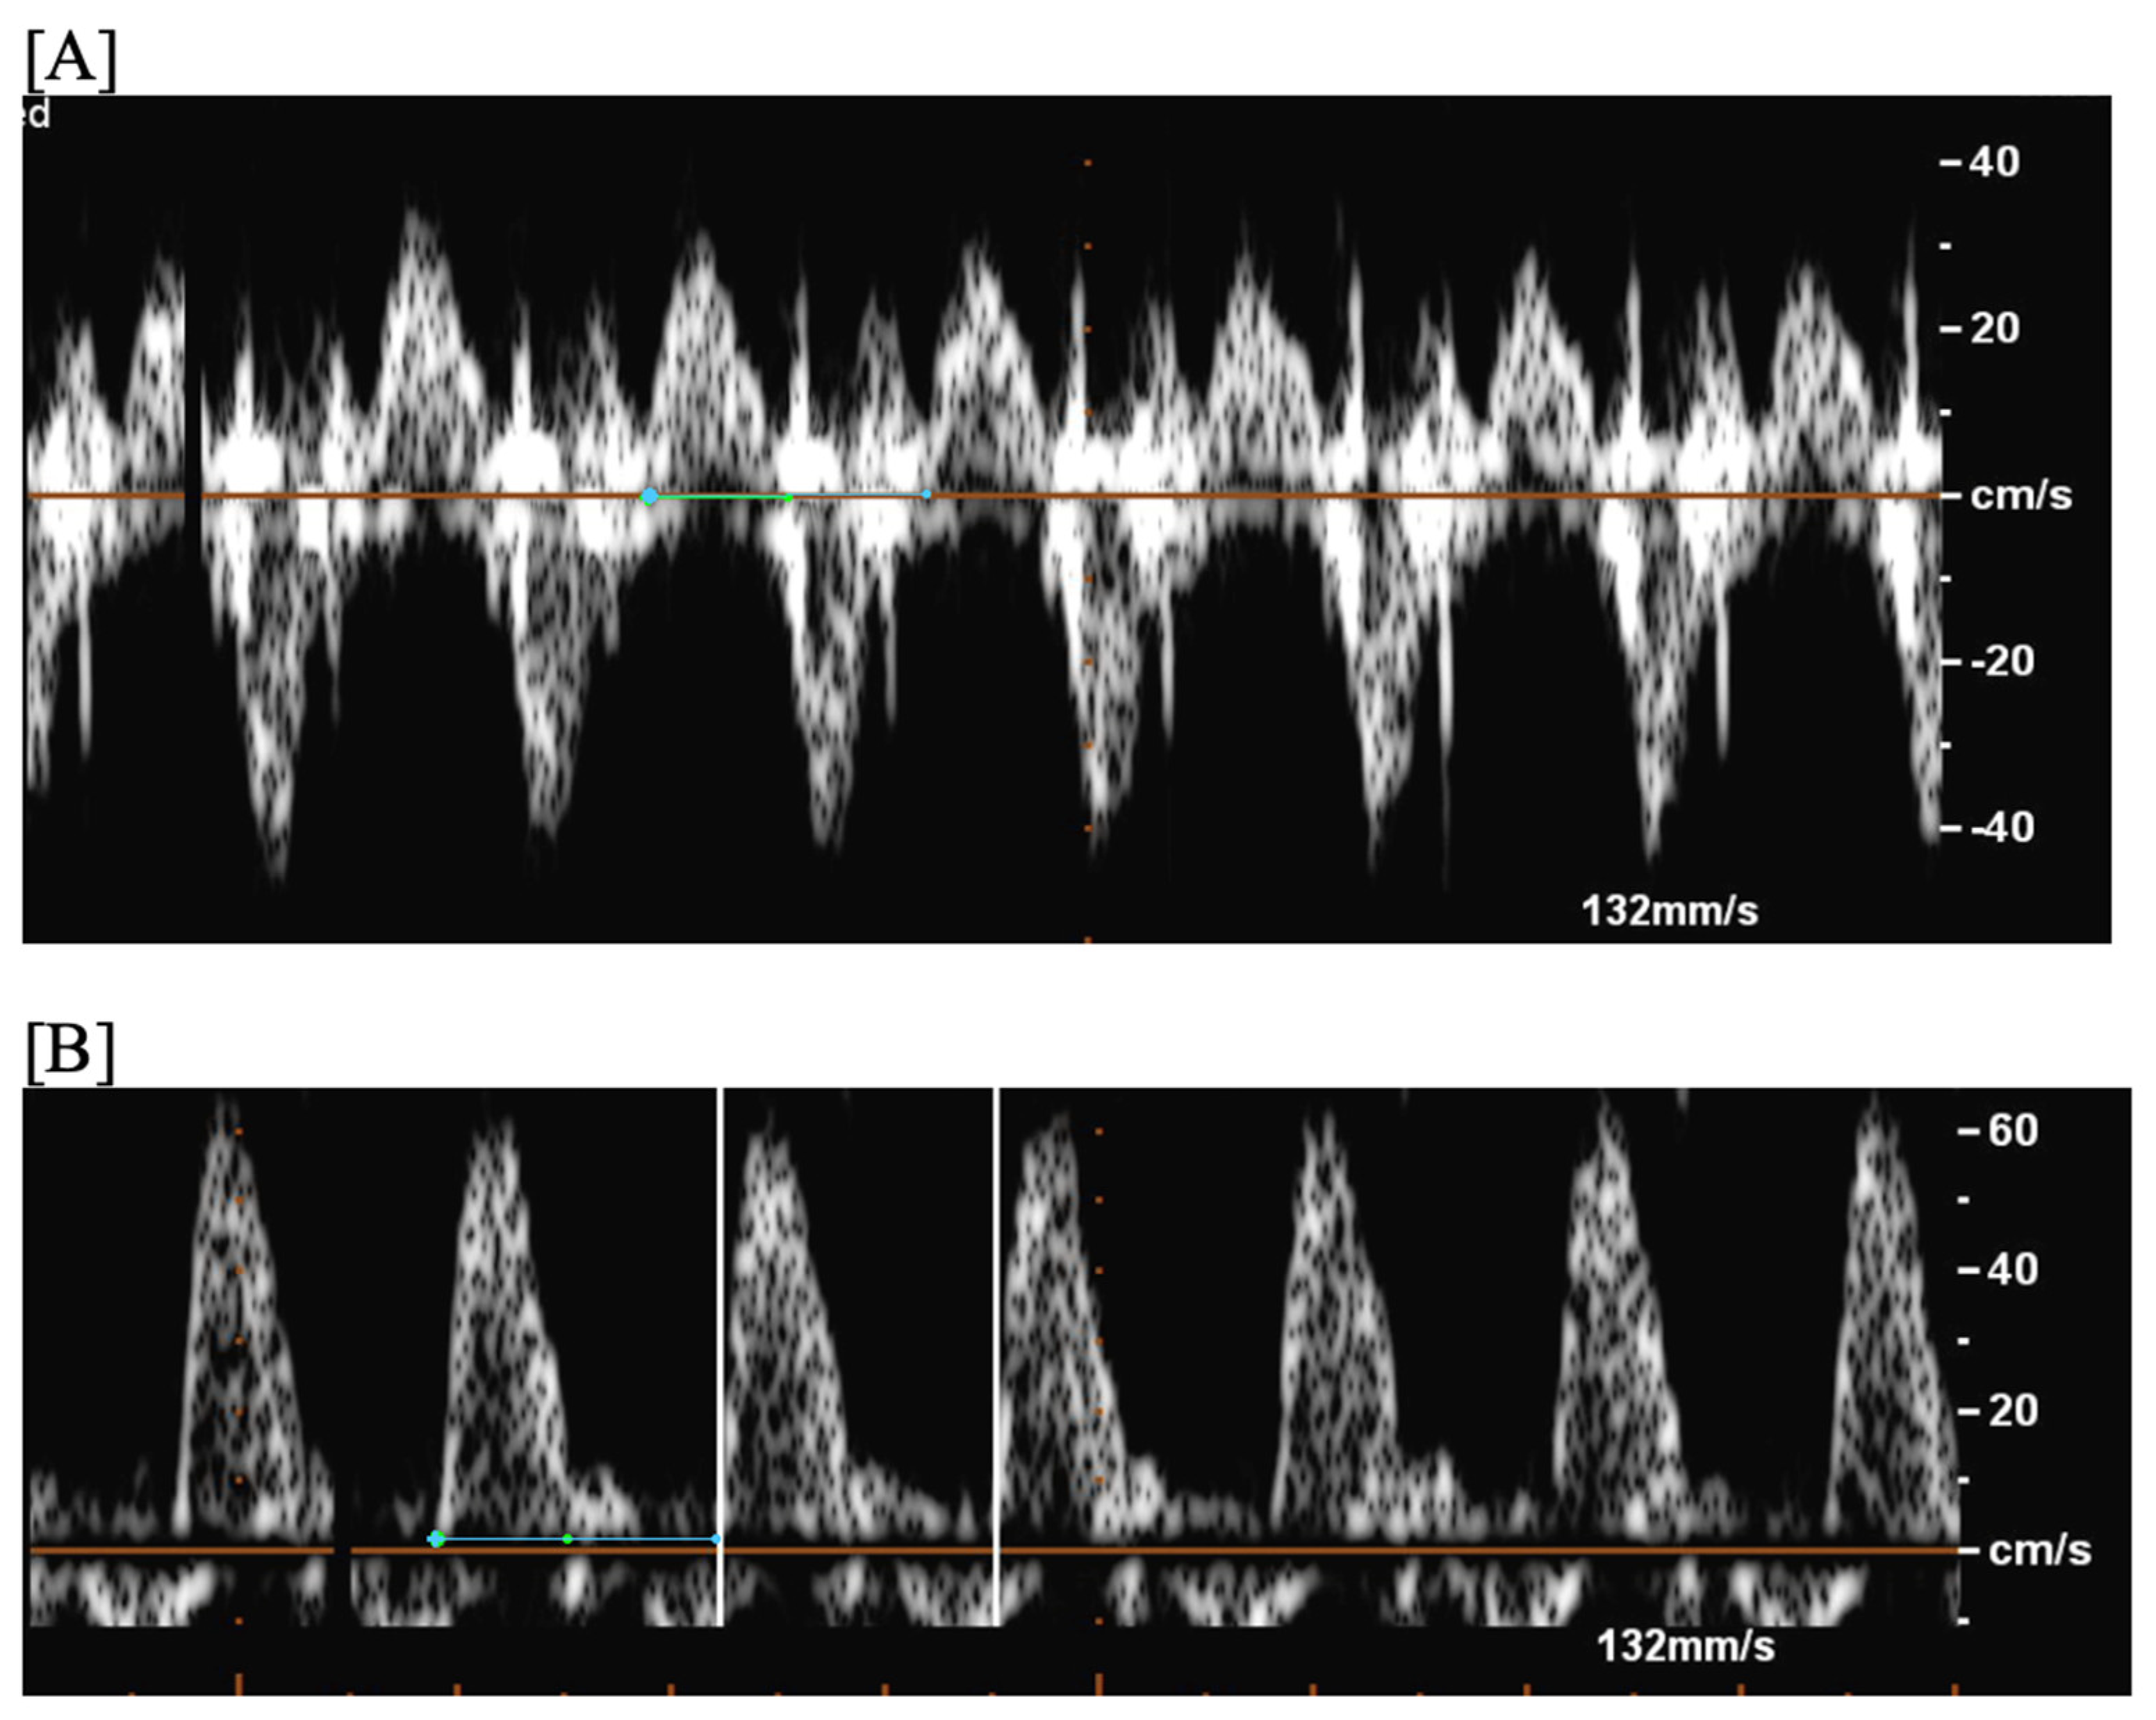

- Short VA SVT (Figure 3 and Figure 4) demonstrates a ventricular–atrial (VA) interval that is less than half of the ventricular–ventricular (VV) interval (VA:AV ratio < 1) and a sudden onset and termination of tachycardia; tachycardia usually terminates with a non-conducted atrial contraction. Short VA SVT includes AVRT (also known as orthodromic reciprocating tachycardia, ORT) and atrioventricular nodal reentrant tachycardia (AVNRT). Short VA SVT typically presents after 18 weeks of gestation.

- Long VA SVT (Figure 4) demonstrates a VA interval that is more than half of the VV interval (VA:AV ratio > 1). Long VA SVT includes EAT and PJRT. A distinguishing feature of EAT is tachycardia termination with ventricular contraction. Long VA SVT may occur as early as 12 weeks of gestation. Because long VA tachycardias have slower rates, they are less likely to cause hydrops.